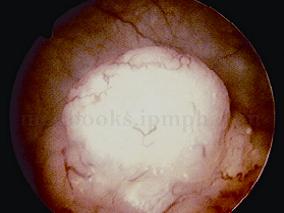

1小时条评论【病例资料】 患者男性,70岁。 主诉:体检B超发现左肾积水10天。 现病史:10天前患者于我院体检,B超提示左肾及左输尿管全长中度扩张积水,左输尿管口黏膜膨出?狭窄?患者无血尿病史,无腰痛、发热,无尿频、尿急、尿痛症状。为进一步诊治于2006年2月22日收入院...